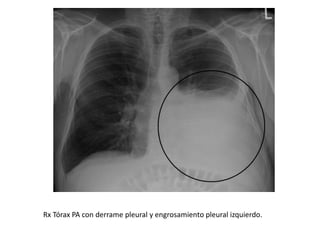

Rx Tórax PA con derrame pleural y engrosamiento pleural izquierdo.

Rx Tórax PAcon derrame pleural y engrosamiento pleural izquierdo.